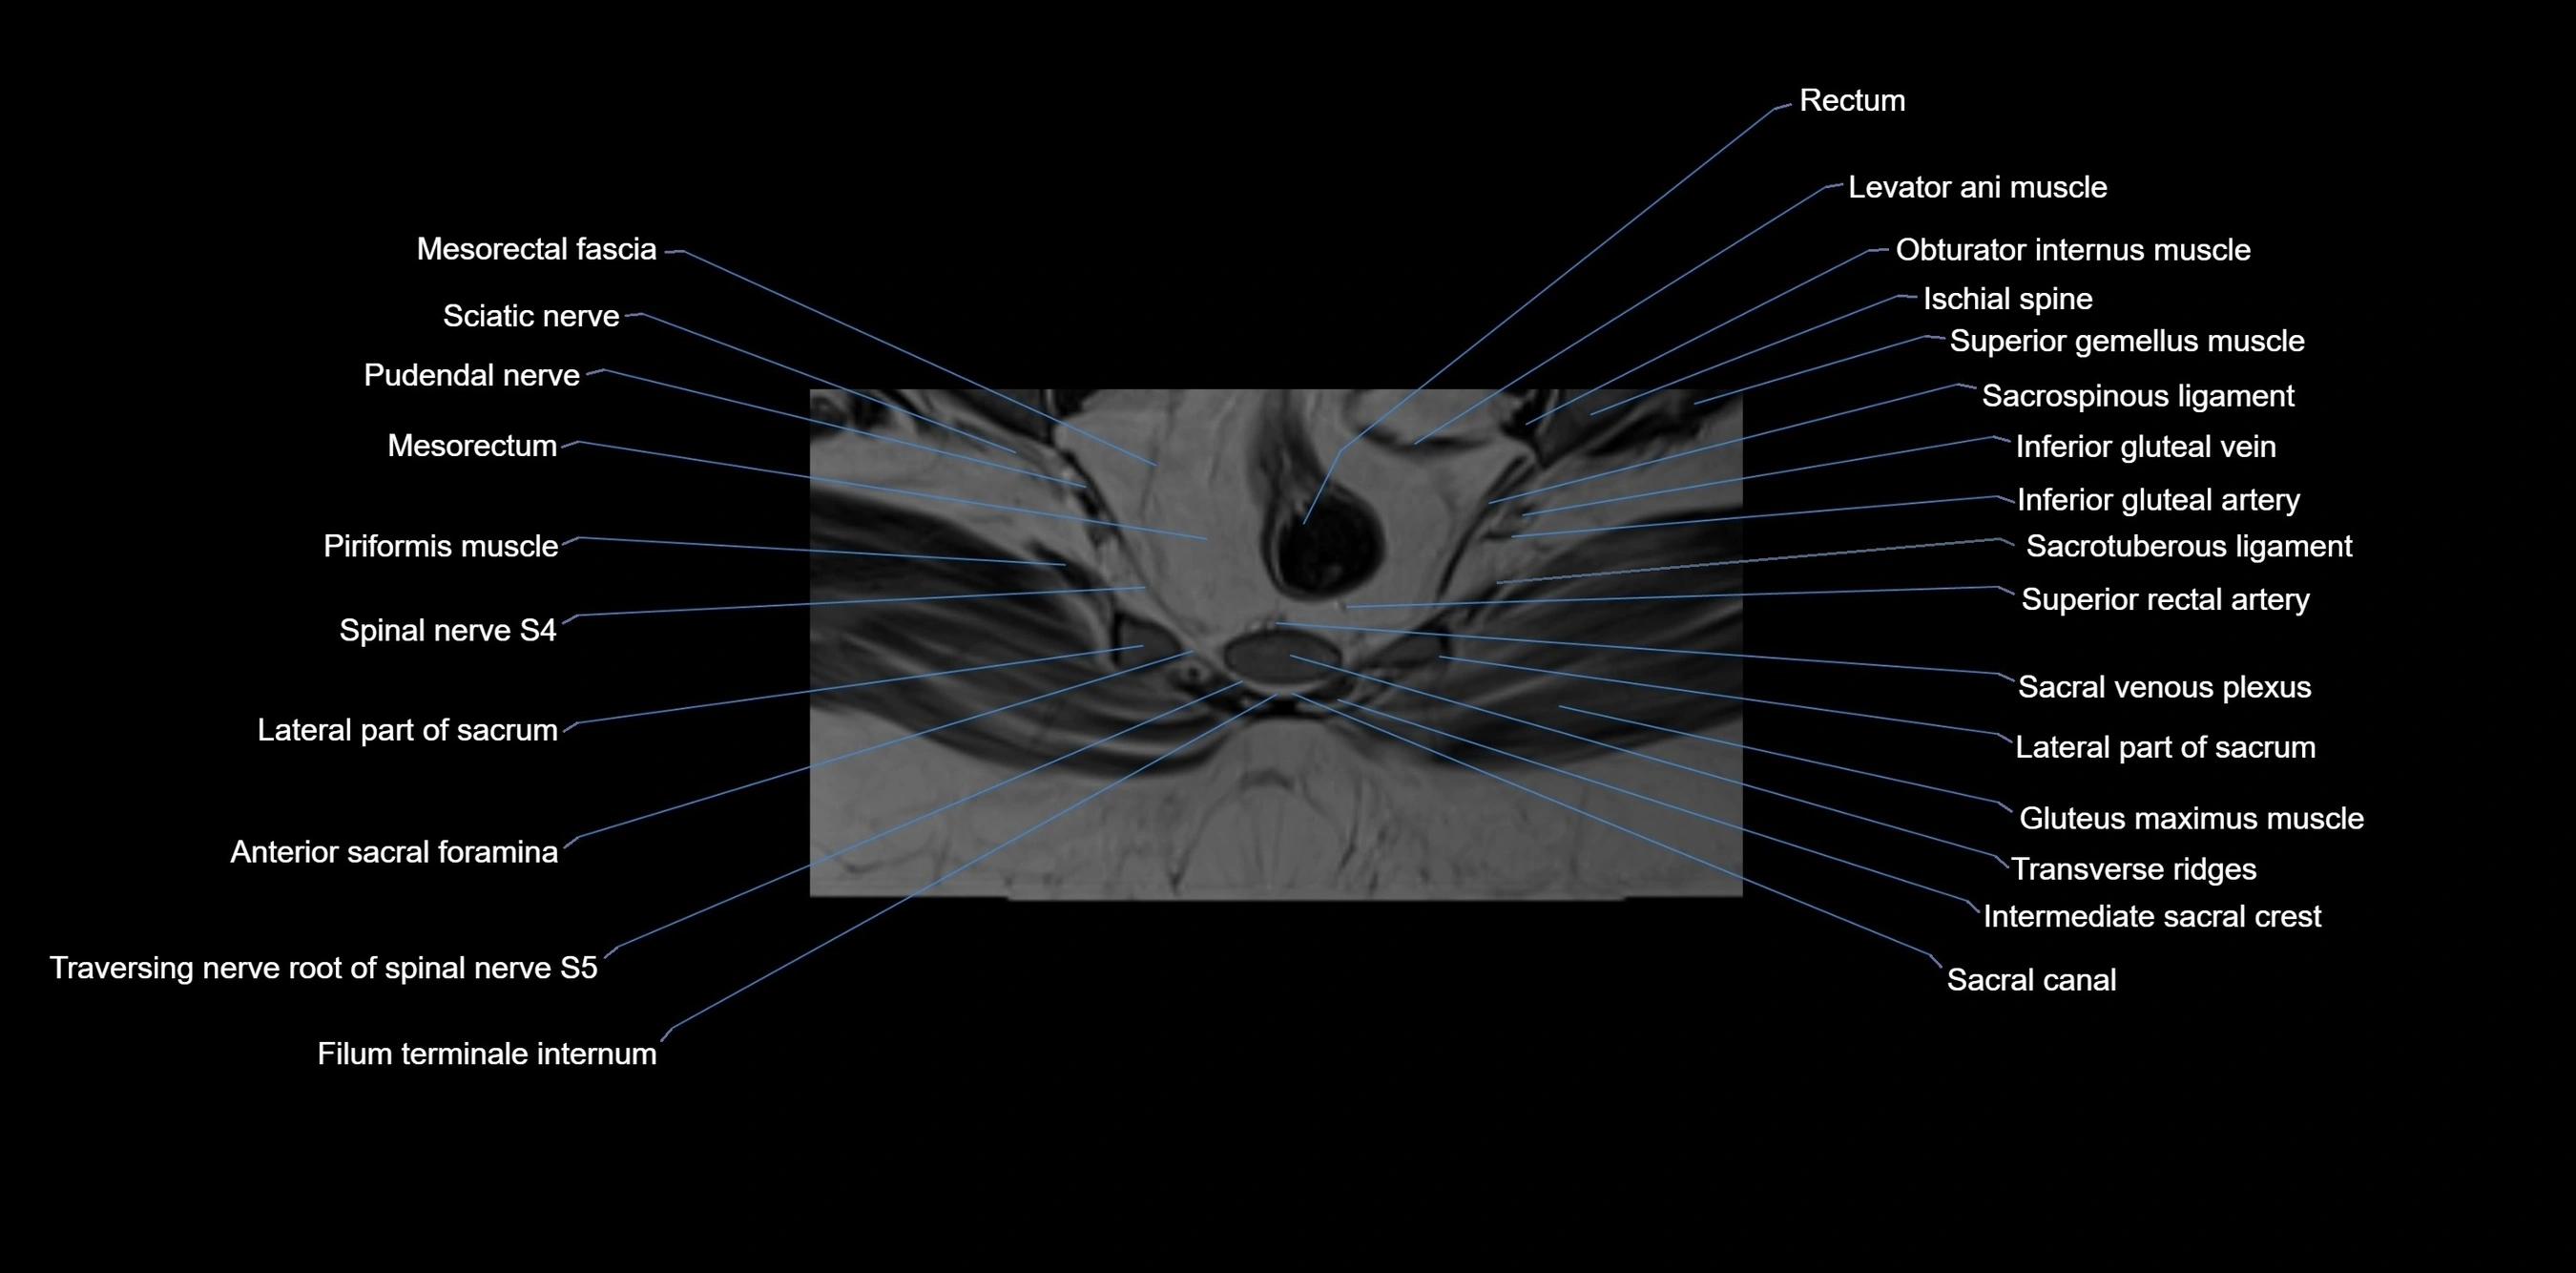

MRI image

image